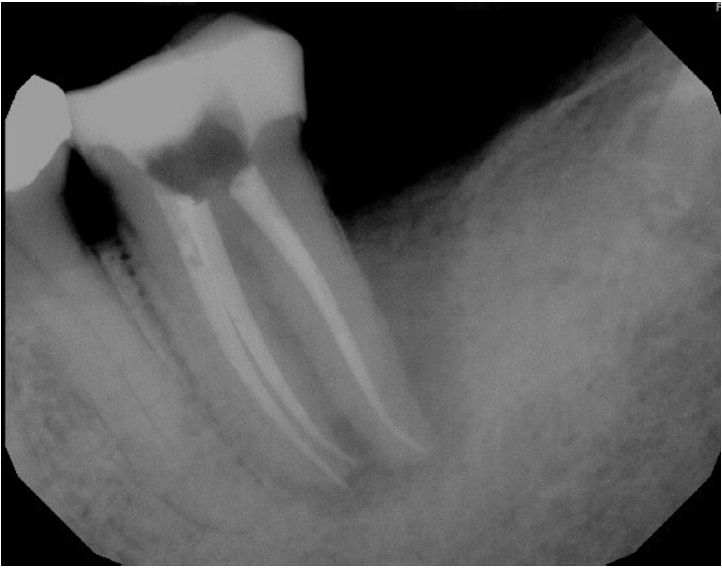

At the 2-week follow-up, the sinus tract had healed. After the same anesthesia and isolation protocol as the first visit, the tooth was accessed through the temporary restoration. Calcium hydroxide was irrigated out with 17% ethylenediaminetetraacetic acid solution, which was ultrasonically activated for 15 seconds in each canal. This was followed by 5% sodium hypochlorite irrigation, which was ultrasonically activated for 15 seconds in each canal, after which cone fit was verified clinically and confirmed with a radiograph (Figure 3). The canals were then dried with paper points, and obturation was completed using gutta-percha cones and AH Plus sealer (Dentsply DeTrey GmbH, Konstanz, Germany) with the cold lateral condensation technique. The tooth was temporized with a sterile sponge and Cavit (3M ESPE) and a postoperative radiograph was captured (Figure 4). A referral for periodontal therapy was given to the patient.

Figure 3.

Cone-fit radiograph.

Figure 3. Cone-fit radiograph.